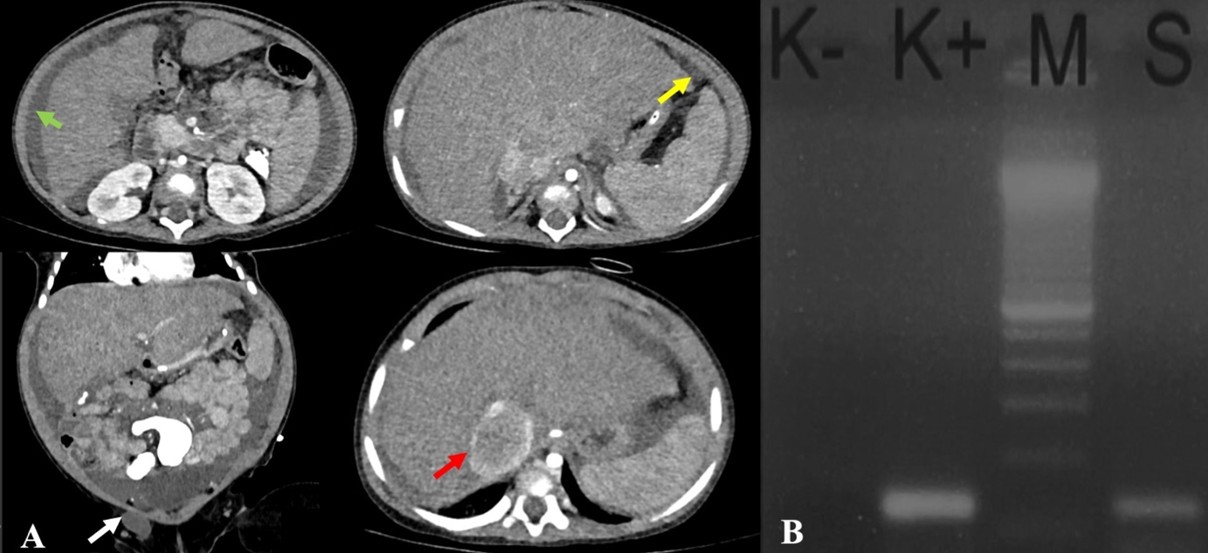

The laboratory results showed microcytic hypochromic anemia with an HGB of 10.00 g/dL and MCV of 65.20 fL. The liver function, bilirubin, and septic markers were normal. An earlier abdominal ultrasound revealed massive ascites. An abdominal CT with contrast revealed ascites in the abdominal and pelvic cavities, dilatation of the inferior vena cava (IVC) due to thrombus formation, a hypodense lesion with peripheral enhancement in the hepatic parenchyma, minimal nodular peritoneal thickening, and reactive lymph nodes in the inguinal regions, suggesting abdominal (hepatic) TB (Figure 5A).

Ascitic fluid analysis revealed a serum-ascites albumin gradient (SAAG) of 1.5 g/dL (transudate). Subsequently, the MTB/RIF Ultra was negative, and the ADA was 20 U/L. Given the inconclusive findings, we opted for in-house polymerase chain reaction (PCR) testing of the ascitic fluid rather than laparoscopy due to the significant ascites. The primers and target gene used for the PCR were provided by our Clinical Microbiology Laboratory, as follows: PCR TB E1 (5′-CCTGCGAGCGTAGGCGTC) and PCR TB E2 (5′-CCGTCCAGCGCCGCTGTCGG), targeting the IS3-like element IS987 family transposase. DNA extraction was performed using the QIAamp DNA Mini Kit, and amplification was carried out with a T100 Thermal Cycler (Bio-Rad) using GoTaq Green Master Mix. The ascitic fluid sample tested positive for TB by PCR, thereby confirming the diagnosis of abdominal TB. The patient completed the intensive phase of ATT with two pediatric fixed-dose combination RHZE tablets once daily for 2 months and entered the continuation phase. (Figure 5B).

The abdominal CT is preferred for detailed visualization, revealing inflammation in abdominal structures and differentiating between TB-related ascites and cancer.15 Abdominal CT can also show peritoneal or intestinal wall thickening, a key feature of abdominal TB.5,16 In a case series in Turkey, the most common findings in abdominal CT were lymphadenopathy, peritoneal thickening, ascites, hepatosplenomegaly, and multiple nodules.11 In Case 2, there was a hypodense lesion with peripheral enhancement in the hepatic parenchyma and minimal nodular peritoneal thickening, which aligns with hepatic TB features.

Molecular testing, including ascitic fluid examination, acid-fast bacilli (AFB) staining, MTB/RIF, and PCR, is crucial in diagnosing abdominal TB. In peritoneal TB, ascitic fluid typically has SAAG < 1.1 g/dL, while SAAG > 1.1 g/dL is commonly seen in patients with cirrhosis or inferior vena cava (IVC) obstruction.17 In Case 2, ascitic fluid analysis revealed a SAAG > 1.1 g/dL, correlating with abdominal CT findings that suggested IVC obstruction as the cause of the transudate pattern. The association between IVC obstruction and abdominal TB is rarely reported, but it may result from acquired IVC thrombosis caused by external compression from swollen retroperitoneal lymph nodes, which distort the IVC and promote thrombus formation.18,19 Consequently, we closely monitored homeostatic function (INR at 1.2) and signs of obstruction.